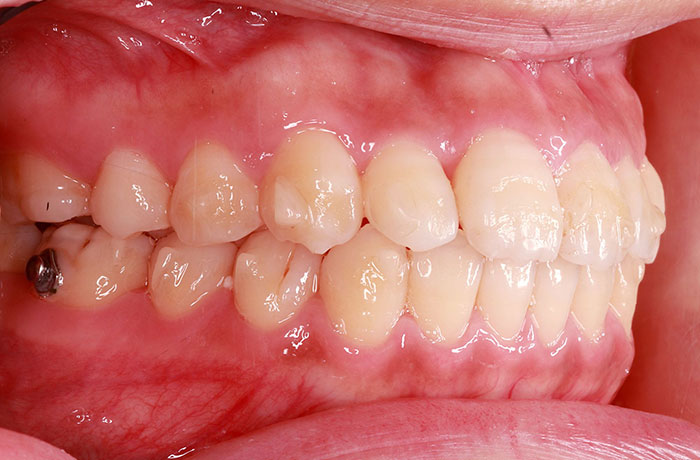

治療前

before

患者の症状 叢生、正中のずれ、上顎左右側切歯の口蓋側転位(交叉咬合)

治療方法 非抜歯で、マウスピース型カスタムメイド矯正歯科装置(インビザライン)による矯正

歯列弓を拡大することで非抜歯を可能にしました。

治療結果 側切歯の交叉咬合は解消、上下正中のずれも改善し咬み合わせが良くなりました。